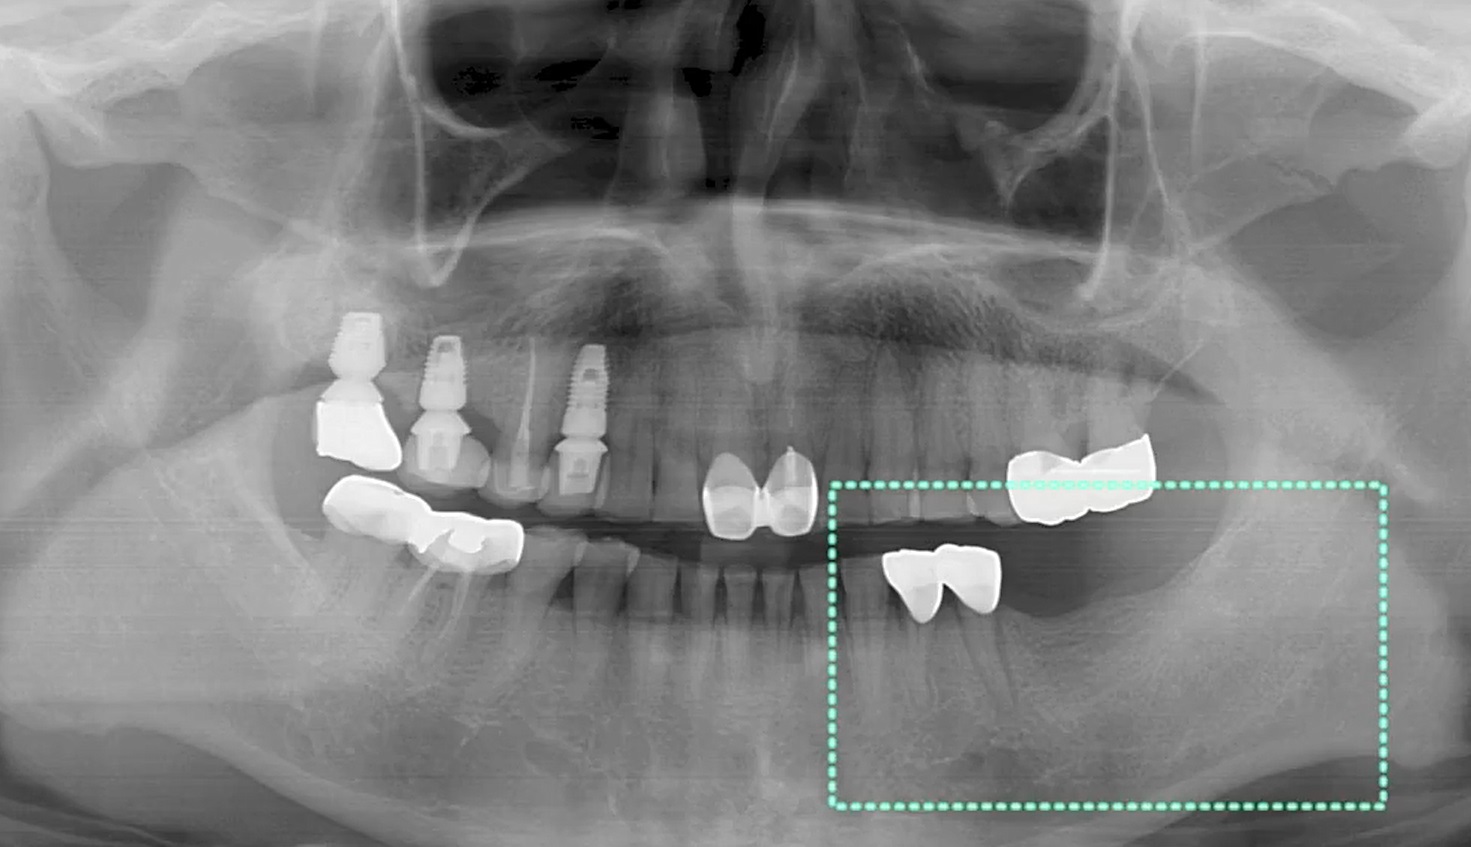

Ten implants placement with predictable computer guided surgery

Dr. NATALIA KOSIUK,Edentulous,Aesthetic zone,Digital Guided Surgery,Immediate loading,Maxillary Anteiror,Maxillary Posterior,#12,#13,#15,#22,#23,#25,#34,#34,#44,#46,Immediate Placement,Flapless,Guided surgery,R2GATE Guide,MEGA ISQ,Poster